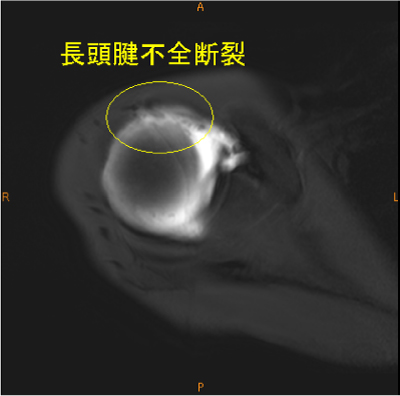

MRI所見

長頭腱の不全断裂は稀な所見である。

MR関節造影で無かったら、描出されて無かった可能性が高い。上方関節唇損傷も認めている。

長頭腱の不完全断裂